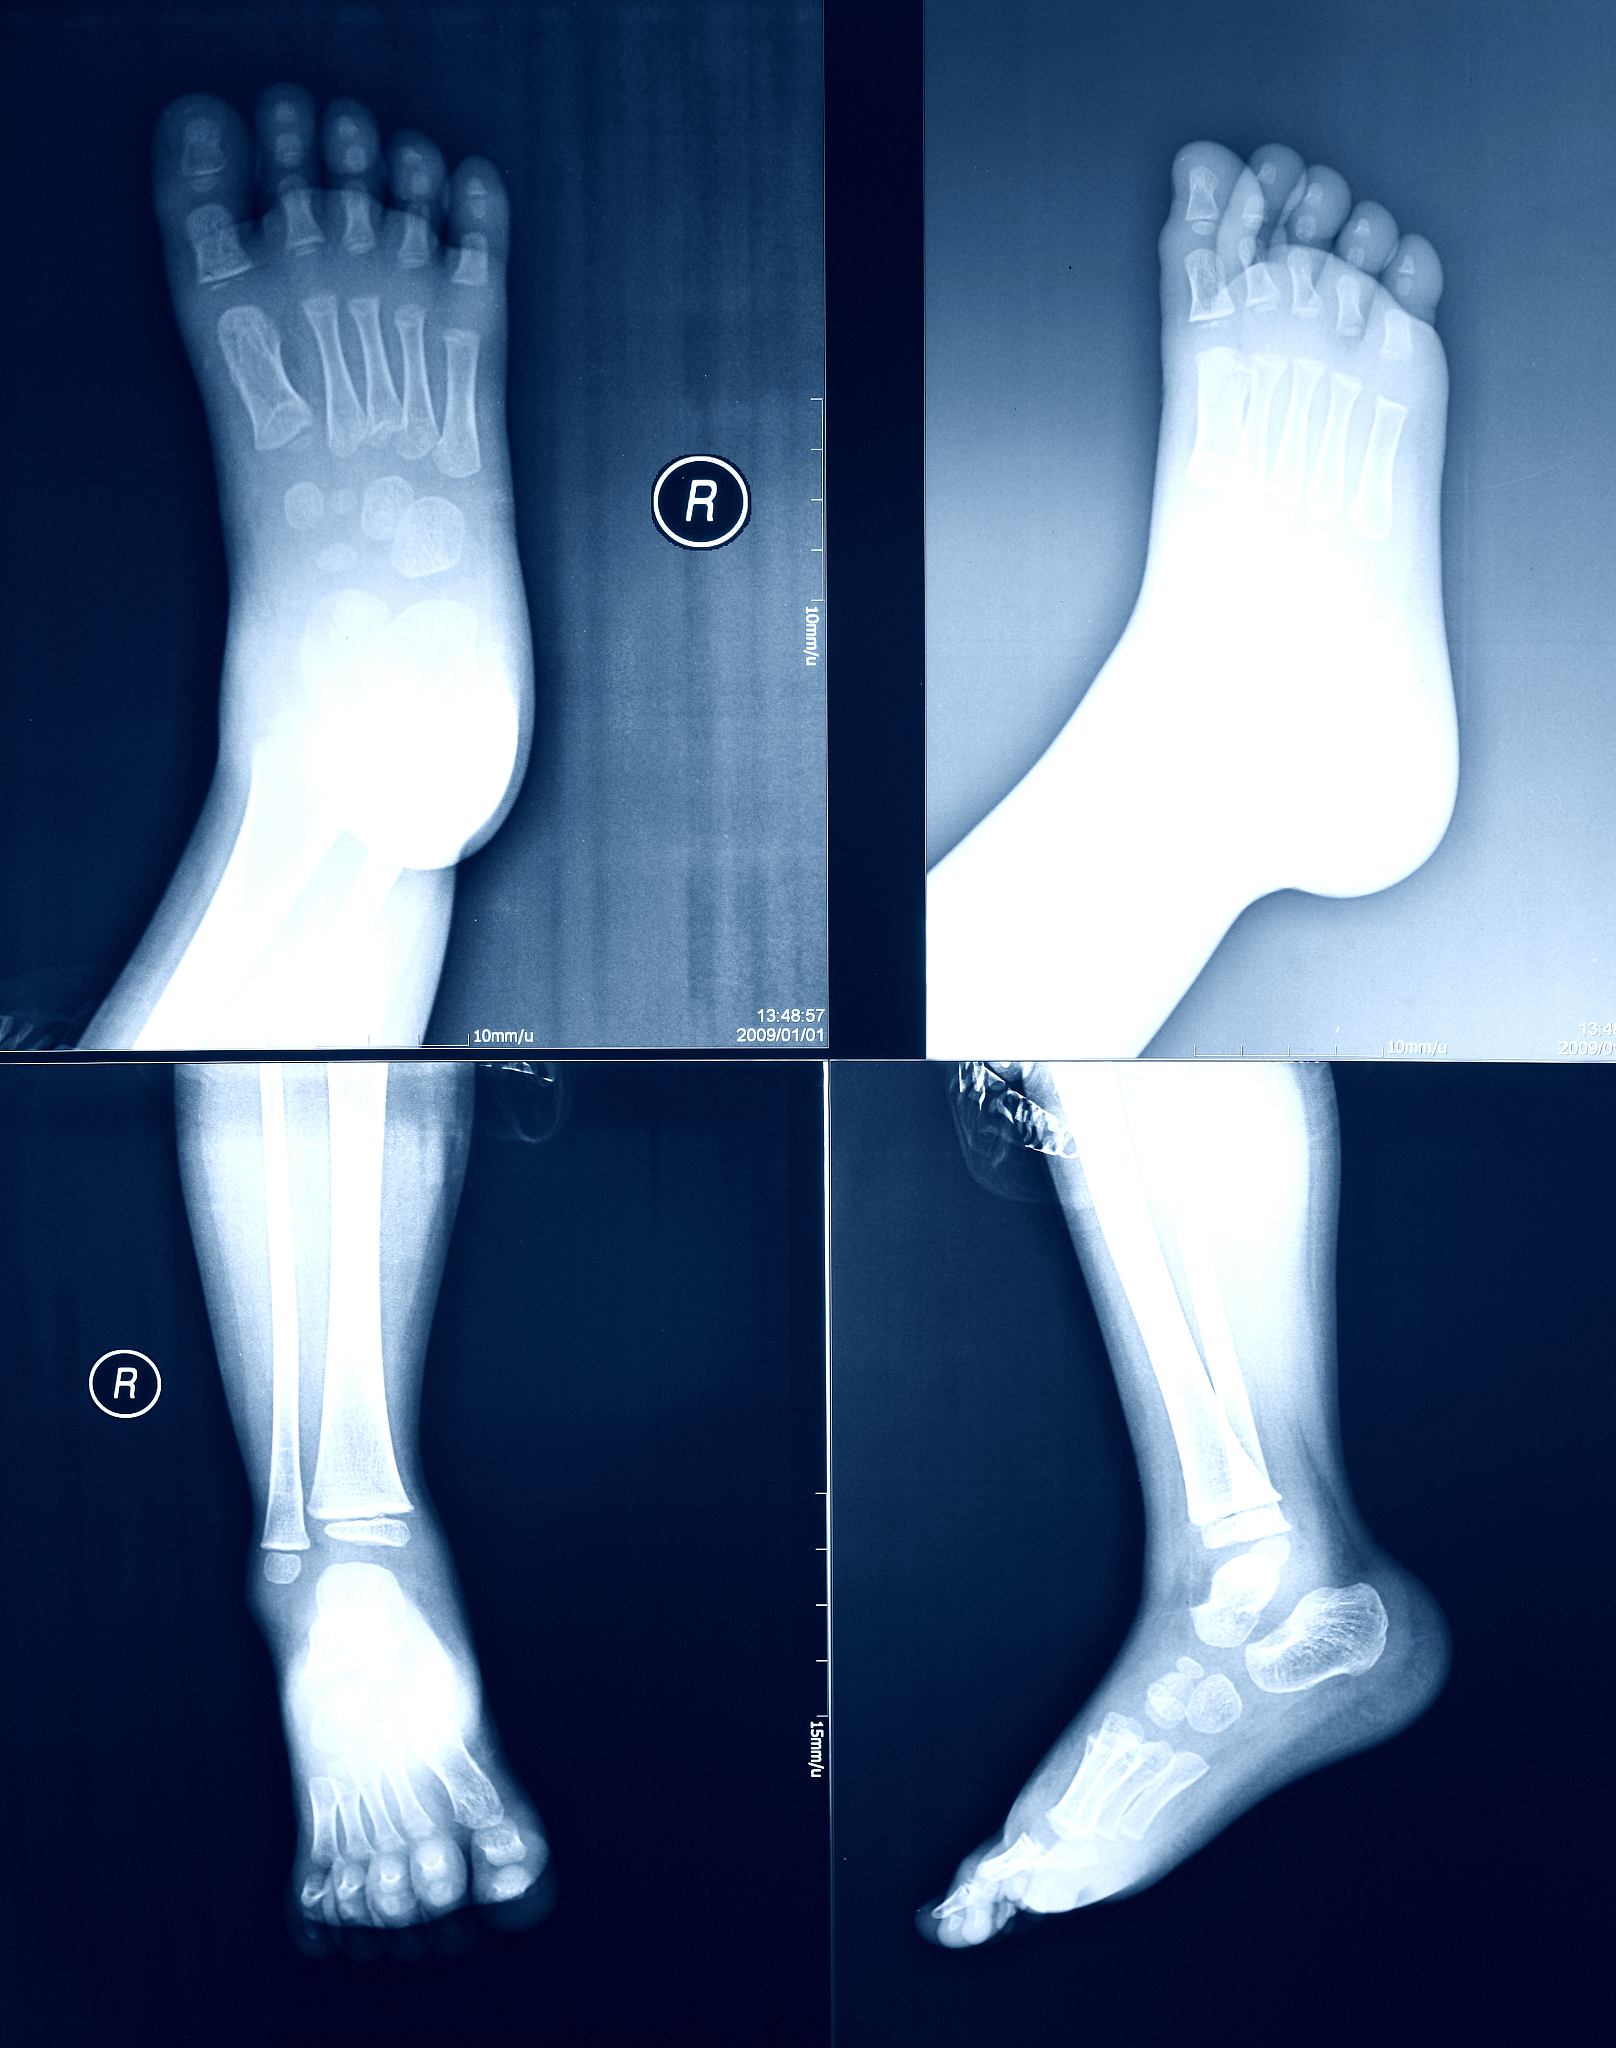

距腓前韧带修复术:简单可靠,稳定疼痛,功能恢复佳

该手术方法专注于修复和紧缩'距腓前韧带',手术操作简单且可靠,术后关节稳定性明显提高,疼痛显著减轻,功能恢复良好,临床效果令人满意。